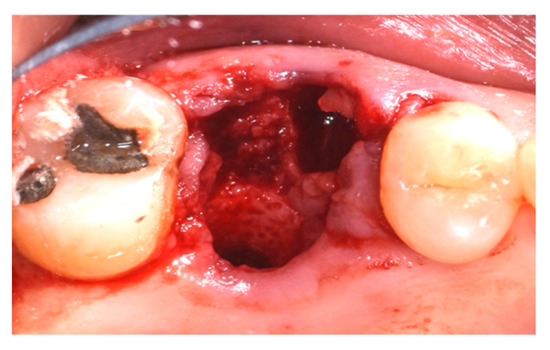

2.4. Surgical Procedure, Evaluation at Follow-Up, and Collection of Radiographic Data

- Measurement in mm of the depth of insertion of the instrument into the gingival sulcus;

- Indicative percentage of dislocation obtained with the Magnetic Mallet® only;